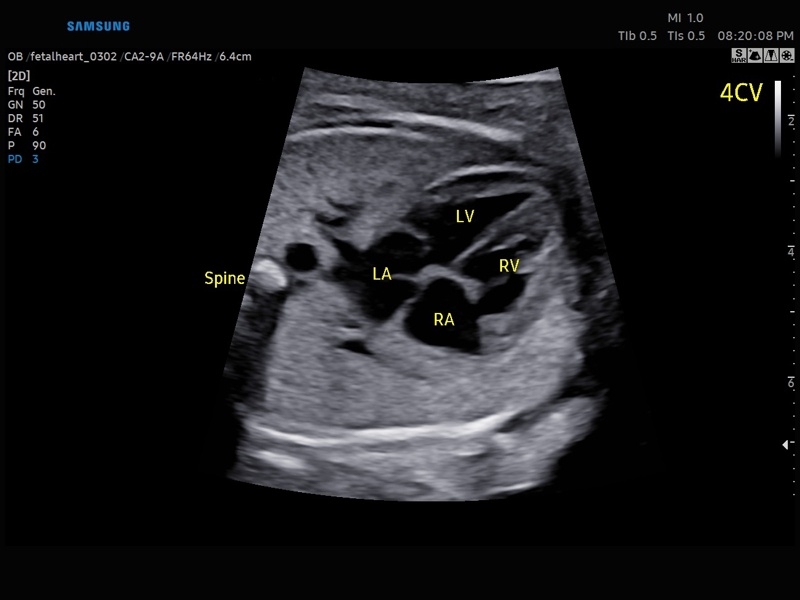

Ультразвуковой сканер V8-RUS является экспертным классом (премиальный уровень) и производится компанией Samsung Medison. Сканер V8 обеспечивает превосходное качество изображения благодаря использованию технологии Crystal Architecture™, которая включает в себя передовое аппаратное обеспечение, монокристальную технологию изготовления датчиков и сложную программную обработку ультразвуковых лучей.

Samsung Medison V8 представляет собой современную ультразвуковую систему, в которой воплощен многолетний опыт компании Samsung в создании эргономичного и интеллектуального диагностического оборудования. Система оснащена передовыми инструментами автоматизации, которые значительно упрощают рабочий процесс и повышают эффективность исследований.

Система Samsung Medison V8 обеспечивает высококачественную диагностику в различных областях медицины:

• Абдоминальные исследования

• Акушерство и гинекология

• Кардиология